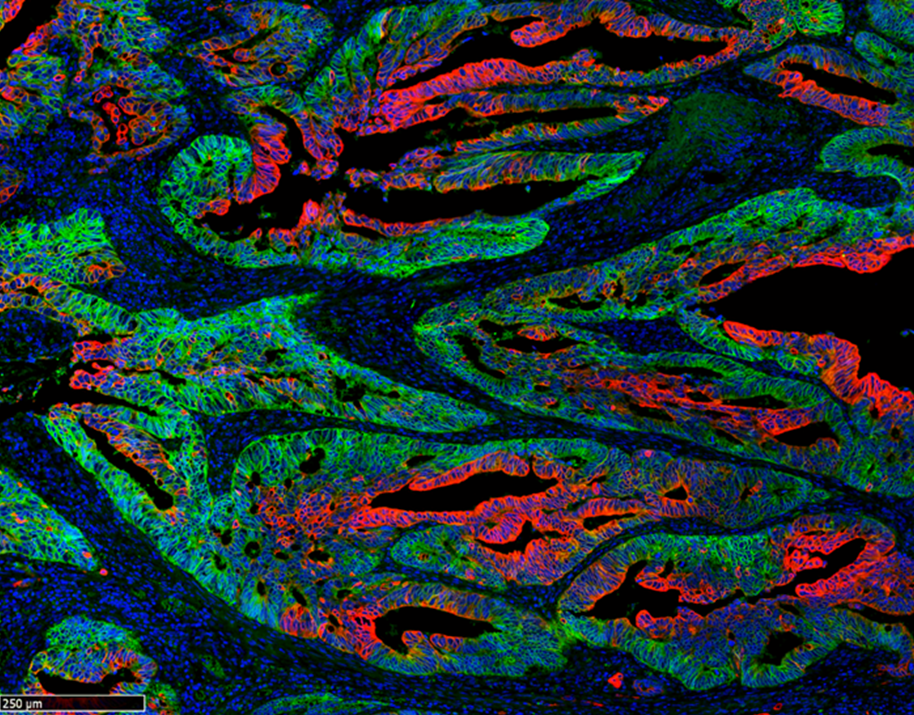

• CIBEREHD

Desarrollan nuevos fármacos para el tratamiento de las enfermedades hepatorrenales poliquísticas

05/05/2020